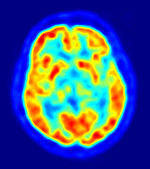

Images of the brain recorded with PET (top) and fMRI (bottom). In the PET image, the red areas are the most active. In the fMRI image, the yellowest areas are the areas that show the greatest difference in activation between two tasks (watching a moving stimulus, versus watching a black screen).

Since one of the focuses of this field is the testing of linguistic and psycholinguistic models, the technology used for experiments is highly relevant to the study of neurolinguistics. Modern brain imaging techniques have contributed greatly to a growing understanding of the anatomical organization of linguistic functions.[2][23] Brain imaging methods used in neurolinguistics may be classified into hemodynamic methods, electrophysiological methods, and methods that stimulate the cortex directly.

Hemodynamic techniques take advantage of the fact that when an area of the brain works at a task, blood is sent to supply that area with oxygen (in what is known as the Blood Oxygen Level-Dependent, or BOLD, response).[29] Such techniques include PET and fMRI. These techniques provide high spatial resolution, allowing researchers to pinpoint the location of activity within the brain;[2] temporal resolution (or information about the timing of brain activity), on the other hand, is poor, since the BOLD response happens much more slowly than language processing.[11][30] In addition to demonstrating which parts of the brain may subserve specific language tasks or computations,[20][25] hemodynamic methods have also been used to demonstrate how the structure of the brain's language architecture and the distribution of language-related activation may change over time, as a function of linguistic exposure.[22][28]